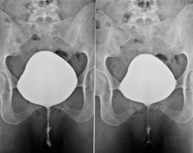

- Cistografía (CUMS)

La cistouretrografía miccional seriada consiste en la obtención de imágenes radiológicas para valorar la anatomía y la función de la uretra y la vejiga con la administración de contraste yodado a través de una sonda vesical.

- Uretrocistografía (Uretro-Cums)

La uretrocistrografía retrógrada y miccional consiste en la obtención de imágenes radiológicas para valorar la anatomía y la función de la vejiga y de la uretra. Se aplica material de contraste a través de una pequeña sonda alojada en la uretra y se obtienen imágenes durante el llenado y vaciado de la vejiga.